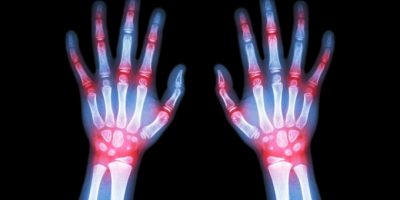

Artrite reumatoide: insorge tra i 30 ed i 50 an...

L’aderenza alla terapia si rivela fondamentale in una patologia cronica come l’artrite reumatoide, caratterizzata da un decorso invalidante che costringe le persone affette all’assenza dal la...